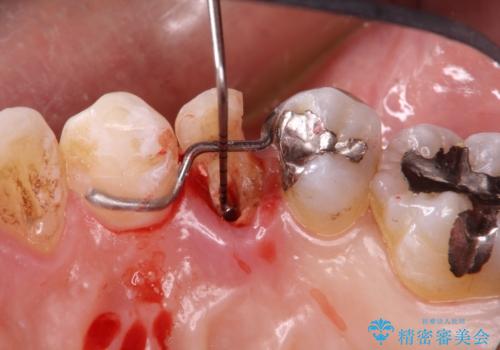

- 歯肉の下まで深く歯が折れたことを主訴に来院された患者様です。

かかりつけ医にて応急的に修復してますが根本的な治療を希望され、矯正的挺出を行ったのち、歯周外科を行い、歯冠修復をしております。

歯肉縁下の水平破折をきちんと治療するためには時間も費用もかかります。